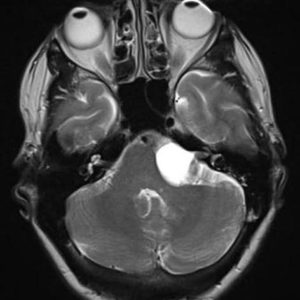

U dây VIII

Lượt xem: 140» 24-11-2018 -

U dây VIII

Lượt xem: 131» 24-11-2018 -

U dây VIII

Lượt xem: 143» 24-11-2018 -

U dây VIII

Lượt xem: 155» 24-11-2018 -

U dây VIII

Lượt xem: 124» 19-11-2018 -

U dây VIII

Lượt xem: 159» 05-11-2018 -

U dây VIII

Lượt xem: 239» 30-10-2018 -